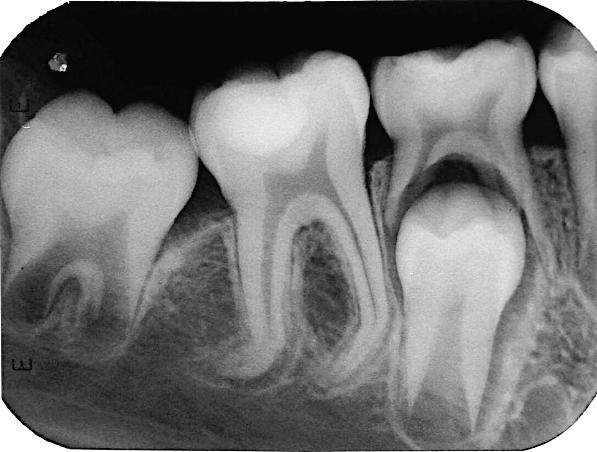

8.Biodentine®AnalternativeinVitalPulpTherapyinYoungPermanentTeeth.ClinicalCase,40monthFollow-Up. (Pgs.88-96)

Biodentine®UnaalternativaenlaTerapiaPulparVitalenDientesPermanentesJóvenes.CasoClínico.Seguimientode40Meses.

LuisDavidRamosFlores,DDS,